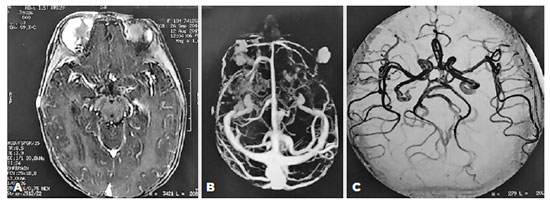

Considering those clinical findings, a diagnosis of PHACE syndrome was made (hemangioma greater than 5 cm plus MGDA). In this way, screening to detect other malformations was performed. Magnetic resonance angiography of the brain and face showed multiple areas of pathological contrast enhancement suggestive of superficial frontotemporal hemangiomas on the right side and a malar on the left side, but cerebral vascular disorders and malformations were not observed (Figure 3). No abnormalities were seen on echocardiogram, abdominal Doppler ultrasound, or electroencephalography. The systemic clinical assessment was normal, except for a glottic hemangioma in the otolaryngologic examination.